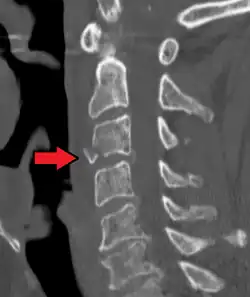

On CT scan or X-ray, a cervical fracture may be directly visualized. In addition, indirect signs of injury by the vertebral column are incongruities of the vertebral lines,[7] and/or increased thickness of the prevertebral space:[8]

![CT scan with upper limits of the thickness of the prevertebral space at different levels[8]](./_assets_/CT_of_prevertebral_space.jpg)